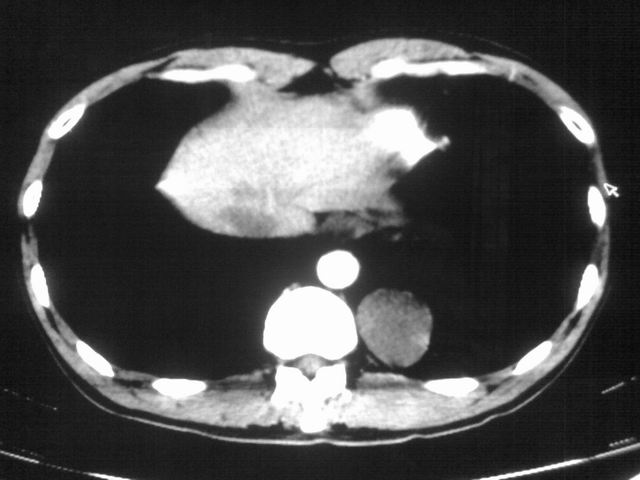

以下是引用苯小孩在2007-4-24 19:46:00的发言:[br]左下肺内侧基底段,见类圆形病灶,边缘清晰光滑.强化后轻中度强化.<平扫第4层面似有从腹主动脉相连血管影,可惜强化扫描这层没有抓住>考虑:左下肺隔离症.建议dsa或薄层强化重建观察.

以下是引用同在2007-4-24 20:11:00的发言:[br]考虑肺隔离症